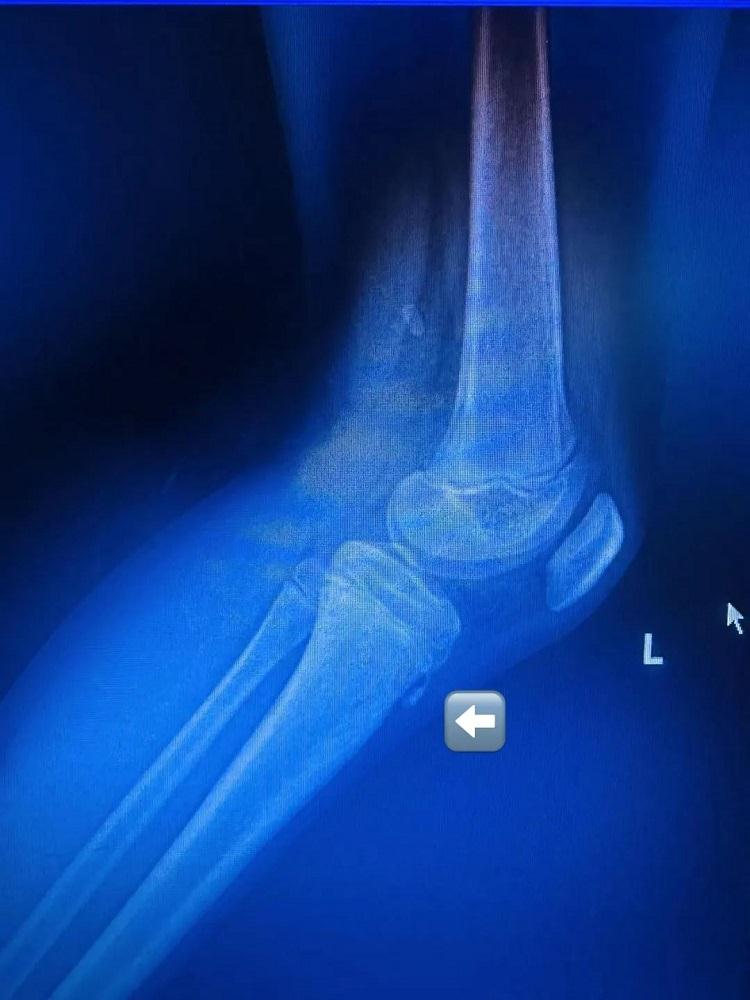

经过运动损伤防治门诊杨晟兴主治医师全面的体格检查与拍片检查,小黄原来是患上了一种名为“胫骨结节骨骺炎”的疾病。通过针对治疗与适当休息,他的膝关节疼痛症状得到有效缓解,胫骨结节骨骺炎也得到了妥善医治。令人意外的是,像小黄这样的小运动员并非个例,击剑高手、羽毛球健将等运动少年也频频中招。

在运动损伤防治门诊,经常会发现有孩子膝盖痛,膝盖前方还可以摸到凸起的骨头,家长担心是否长了“不好的东西”。经过检查,发现这些孩子大部分是患上了专病门诊常见的疾病:“胫骨结节骨骺炎”或“胫骨结节骨软骨病”。

胫骨结节骨骺炎是青少年群体中较为常见的一种膝关节疾病。其发病机制主要是胫骨结节骨骺在髌腱反复牵拉下受损。该病多见于 11 - 15 岁的青少年,特别是那些热爱运动的男孩,主要表现为胫骨结节部位疼痛与肿胀。

胫骨结节是膝盖下方胫骨顶端的一个骨性凸起,是髌腱(连接膝盖骨与小腿骨的肌腱)的附着点。青少年时期,此处的骨骺(骨骼生长板)尚未完全闭合,处于脆弱阶段。当髌腱反复牵拉胫骨结节,可能导致局部微小损伤、炎症甚至骨骺撕裂,从而引发疼痛和肿胀。